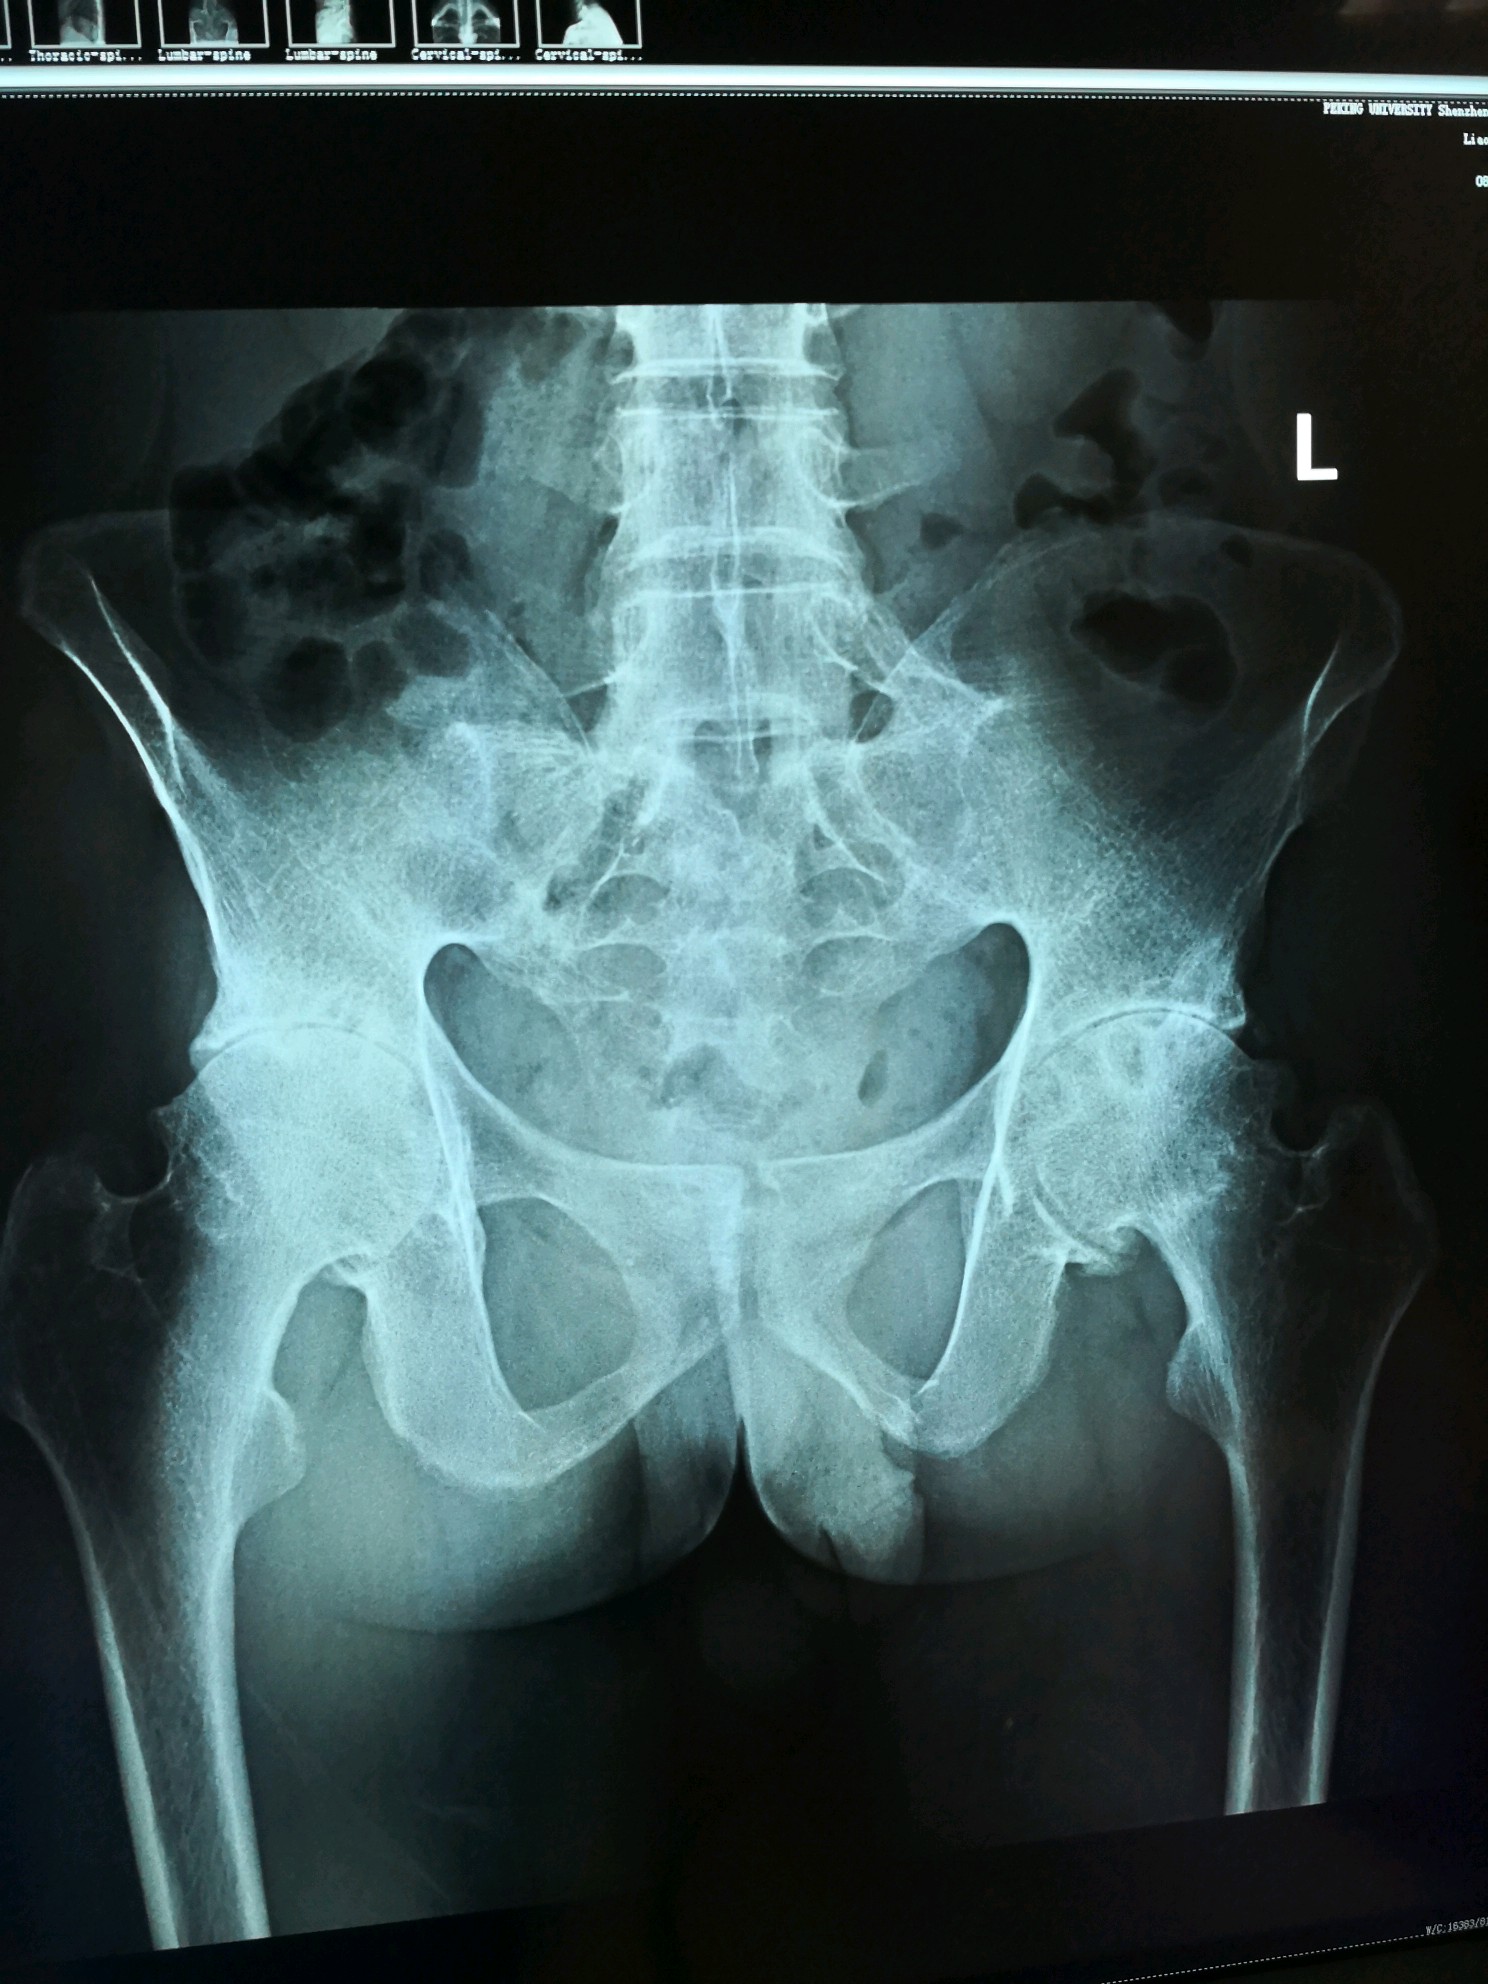

患者28岁男性,患强直性脊柱炎多年,现双髋部疼痛,行走时加重,双髋关节屈伸活动受限,双下肢不能外展。颈椎及腰椎活动尚好。为提高生活质量,可以从事日常工作及生活,住院手术治疗,一次性行双侧髋关节置换手术。采用进口陶对陶关节。术后恢复良好。

术前双髋正位片